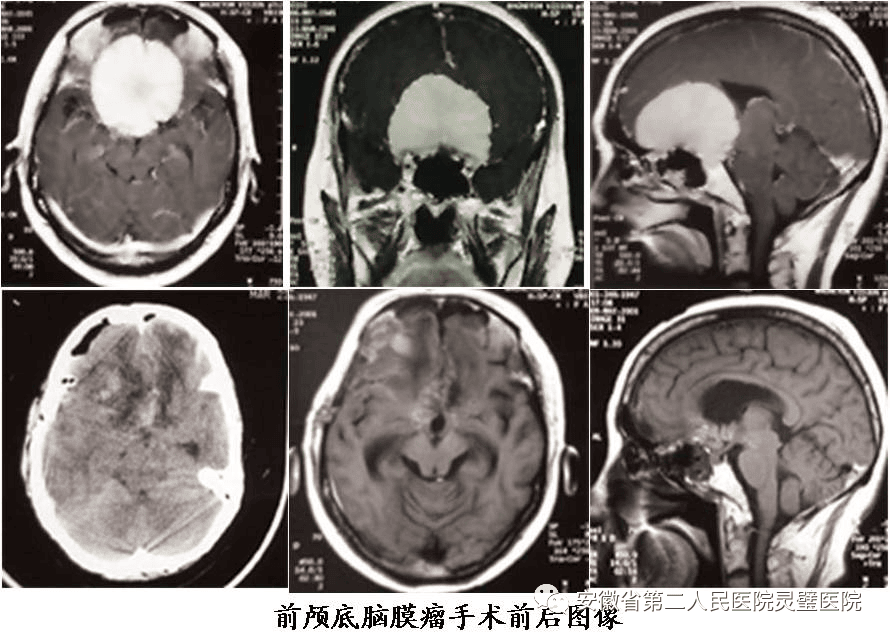

二、神经肿瘤的综合治疗技术

常规开展各型颅内及脊髓肿瘤手术,包括鞍区肿瘤、斜坡肿瘤、后颅窝等颅底肿瘤,尤其在听神经瘤、颅咽管瘤、垂体瘤等治疗方面处于国内领先水平。系统开展胶质瘤的综合治疗,并结合肿瘤基因指标,提升胶质瘤的放化疗效果,极大提高5年的存活率。

岩斜区脑膜瘤术前及术后